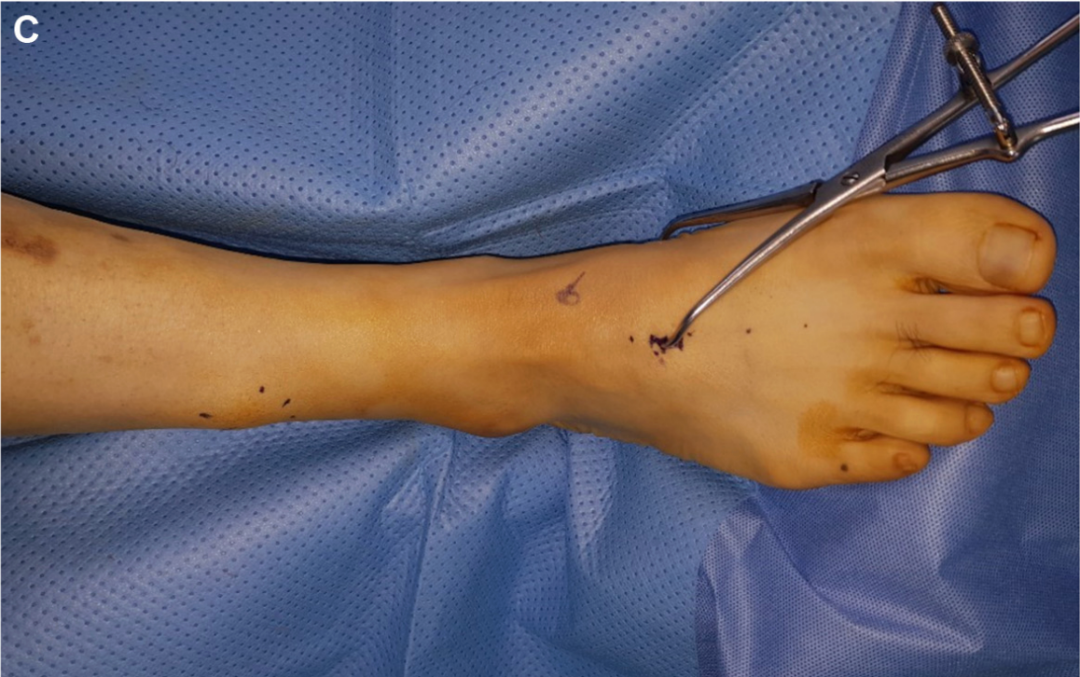

▲图示内侧皮肤切口。

▲图示若手法复位效果不佳,则应用复位钳辅助复位。